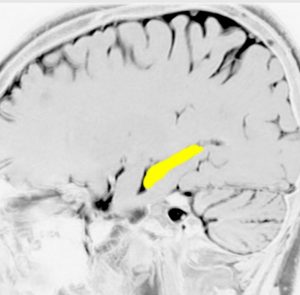

海馬

両側の側頭葉の内側にあり,学習,記憶,空間認識(spartial awareness。物体のある場所・大きさ・形・速さ・向き・物体同士の位置関係などを素早く正確に認知する能力)を司ります

記憶に関しては左側の海馬に優位性が大きいです

左の海馬を横から見たところです

記憶の中枢であり,この部位の機能低下は認知症を招きます

アルツハイマー病の原因ともなる部位です